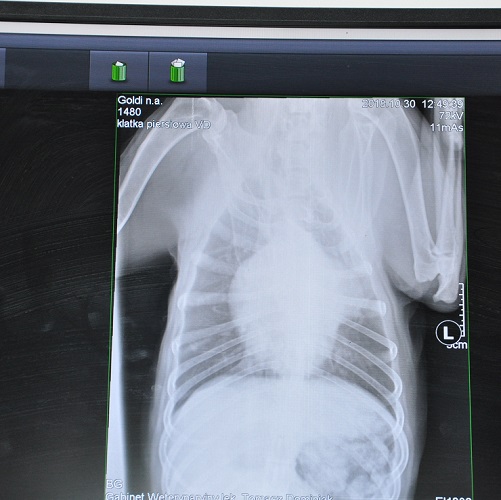

Kilka dni temu byliśmy z Goldim w lecznicy, u boksera znowu pojawił się problem z kaszlem. Lekarz wykonał zdjęcia RTG klatki piersiowej, żeby sprawdzić, czy Goldi nie ma problemu z oskrzelami albo płucami.

Niestety okazało się, że problem jest bardziej poważny, ponieważ zdjęcie RTG wykazało obecność zmiany nowotworowej przy sercu. Goldiego czeka wizyta u kardiologa.

Goldi był dzisiaj na wizycie u kardiologa. Wykonano mu badanie echokardiograficzne serca, które wykazało widoczną zmianę rozrostową przylegającą do łuku aorty i lewego przedsionka.

Kilka dni temu byliśmy z Goldim w lecznicy, u boksera znowu pojawił się problem z kaszlem. Lekarz wykonał zdjęcia RTG klatki piersiowej, żeby sprawdzić, czy Goldi nie ma problemu z oskrzelami albo płucami.

Niestety okazało się, że problem jest bardziej poważny, ponieważ zdjęcie RTG wykazało obecność zmiany nowotworowej przy sercu. Goldiego czeka wizyta u kardiologa.

Goldi był dzisiaj na wizycie u kardiologa. Wykonano mu badanie echokardiograficzne serca, które wykazało widoczną zmianę rozrostową przylegającą do łuku aorty i lewego przedsionka.